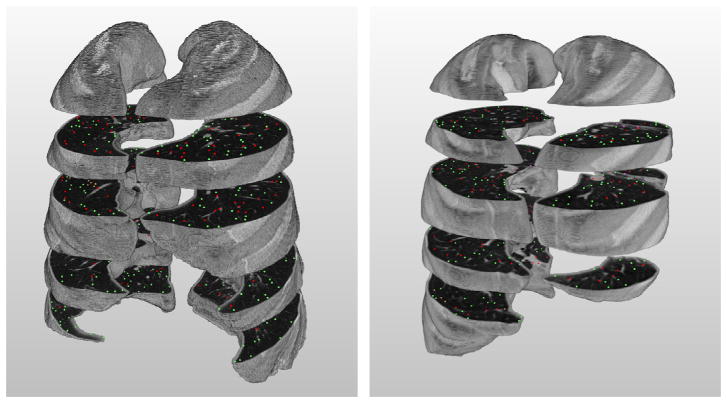

Fig. 2.

Illustration of the slices and annotated POIs in scan 01 (left) and 06 (right) after labeling process; red points indicate those which are marked as vessels, green non-vessels. (For interpretation of the references to color in this figure legend, the reader is referred to the web version of this article.)